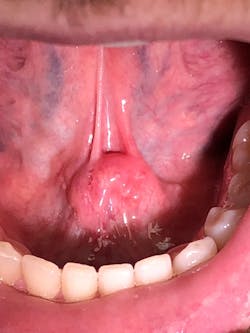

During an oral cancer screening, a soft-tissue lesion was noted on the floor of the mouth at the junction of the ventral surface of the tongue (figure 1).

The lesion was offset to the left, but appeared to cross the midline based upon the position of the frenum. The lesion was about 1.5 cm x 1 cm. Upon palpation, the tissue was firm but not indurated and mobile as one mass. The patient reported no symptoms other than mild discomfort upon palpation (figure 2). When asked about the duration of the lesion, the patient stated he had been aware of it for around two to three weeks, but it was not bothering him.